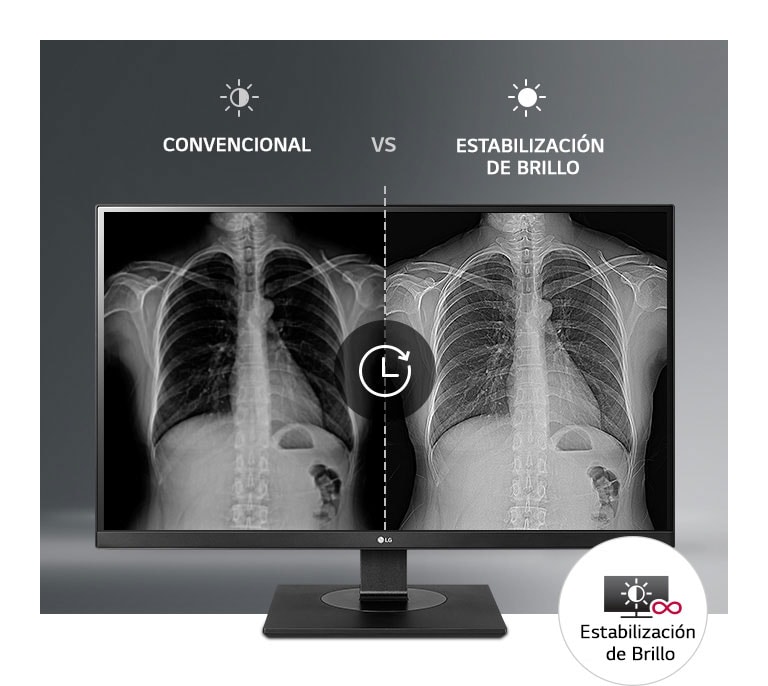

Imágenes Médicas con Consistencia Asegurada

Estabilización del brillo

SIM